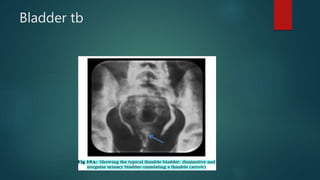

Bladder tb